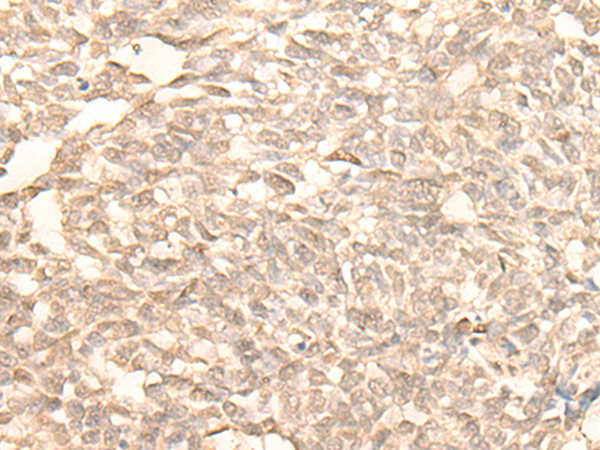

分类: 科研抗体货号: P02715别名: ACAD2应用: IHC反应种属: Human, Mouse, Rat